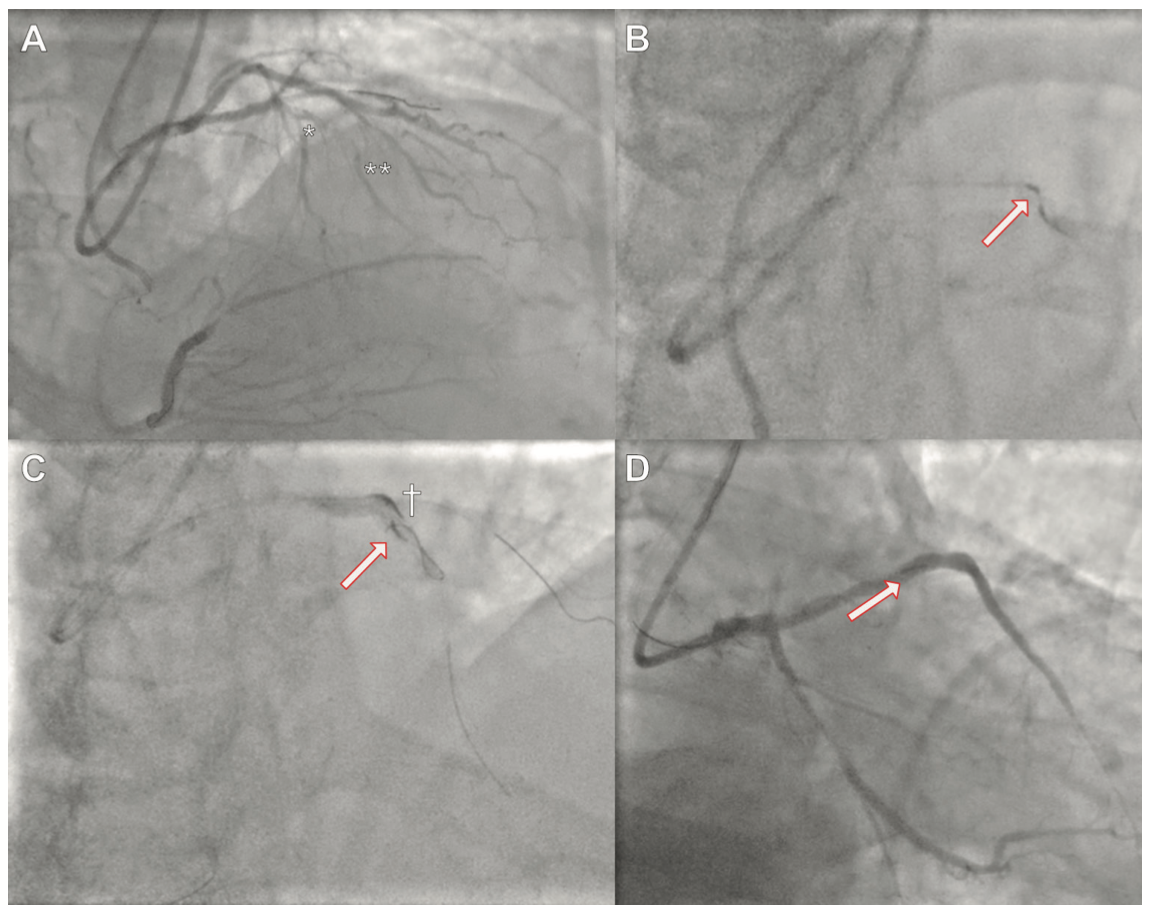

Case 1. A 78-year-old male with class III Canadian Cardiovascular Society (CCS) angina was discussed at the local heart team meeting. Past medical history comprised atrial fibrillation, previous permanent pacemaker implantation and coronary artery bypass graft surgery (>20 years ago) with left internal mammary artery to the left anterior descending (LAD) artery and second diagonal (D2) as jump graft (patent), saphenous vein graft (SVG) to the first diagonal (D1; patent, stented), and SVG to the posterior descending artery (PDA; occluded). The native right coronary artery (RCA) was chronically occluded in its mid to distal segment (Figure 1A). There was retrograde collateral supply to the distal PDA from a branch of the first obtuse marginal (OM1; via SVG), which itself originated at the location of a severe lesion in the proximal circumflex (LCX) artery. The inferior wall was viable on echocardiography and, in light of limiting angina, the heart team recommended PCI to the CTO of his native RCA (J-CTO score 2).

With biradial 7-Fr access and Amplatz Left 1 catheters in both the native RCA and the occluded SVG, we followed the hybrid algorithm and were successful in wiring the true lumen distally with antegrade wire escalation, using a Gladius MG14 (Asahi Intecc). The proximal cap, however, proved uncrossable and the microcatheter (Turnpike Spiral; Teleflex) became stuck and disintegrated upon retrieval, leaving the tip within the occlusion (Figure 1B). Attempts to dilate the proximal cap using a 1.0 balloon in order to release the tip of the microcatheter proved unsuccessful. Rewiring the true lumen distally using a Turnpike Gold microcatheter (Teleflex) and Gladius Mongo wire was attempted but failed, and the “scratch and go” technique using a Confianza Pro 12 wire (Asahi Intecc) to puncture the vessel wall proximal to the occlusion to gain access to the subintimal space also failed. We subsequently employed the balloon-assisted subintimal entry (BASE) technique with a 4.0-mm balloon proximal to the occlusion to create a controlled dissection and advance a knuckled polymer-jacketed wire (Gladius MG14; Asahi Intecc) around the occlusion (Figure 1C). Antegrade dissection re-entry (ADR) attempts with the use of a dedicated Stingray balloon (Boston Scientific) and utilizing the initial wire as a marker of the true lumen failed due to heavy calcification at the level of the previous SVG touchdown. We subsequently escalated using stick and drive (Hornet 14 [Boston Scientific]; Astato 20 [Asahi Intecc]; and Stingray wires) and stick and swap (Pilot 200 wire; Abbott Vascular) techniques, all of which failed due to angulation and heavy calcification. A retrograde attempt with a Turnpike LP 150 wire (Teleflex) via SVG-D1 failed due to extreme angulations preventing the successful wiring of the septal collaterals despite the use of an angulated Supercross 120 microcatheter (Teleflex). We then attempted to use retrograde access from the occluded SVG-PDA, but were unable to wire retrogradely due to angulation and lack of distal visualization. However, the retrograde microcatheter in the PDA was then used as a marker of the distal true lumen for a further attempt at ADR, which proved successful after predilating the subintimal track with a 1.0 balloon to allow for delivery of a new Stingray balloon to the PDA. Stick and drive technique with a Hornet 14 wire was successful, as confirmed via tip injection from the retrograde microcatheter. The native RCA was eventually stented under intravascular ultrasound (IVUS)-guided sizing and optimization using 2.5 x 28-mm, 3.5 x 38-mm, and 4 x 28-mm drug-eluting stents. With this approach, the retained microcatheter tip was jailed between the stent and vessel architecture and was hence excluded from the newly formed vessel lumen. The very distal vessel was optimized using a 2.5 x 30-mm drug-eluting balloon (Figure 1D).